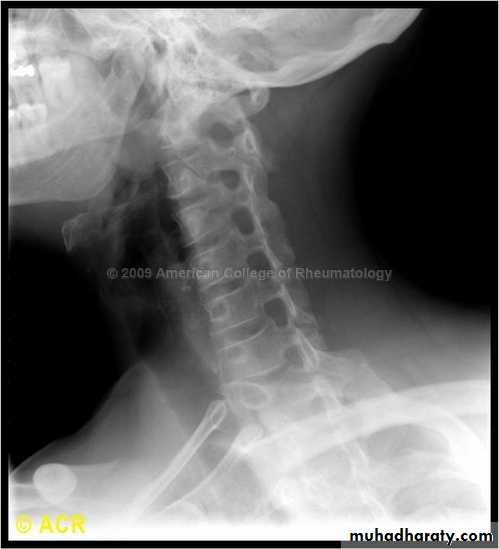

DIAGNOSISX RAY

Anterio posterior X ray radiograph.lateral radiographs with the head in flexion and extension may revealinstability that is not shown in the routine lateral film.

oblique views

at 45° are especially helpfula special projection

through the open mouth.Computed tomography (CT)

and magnetic resonance imaging (MRI).